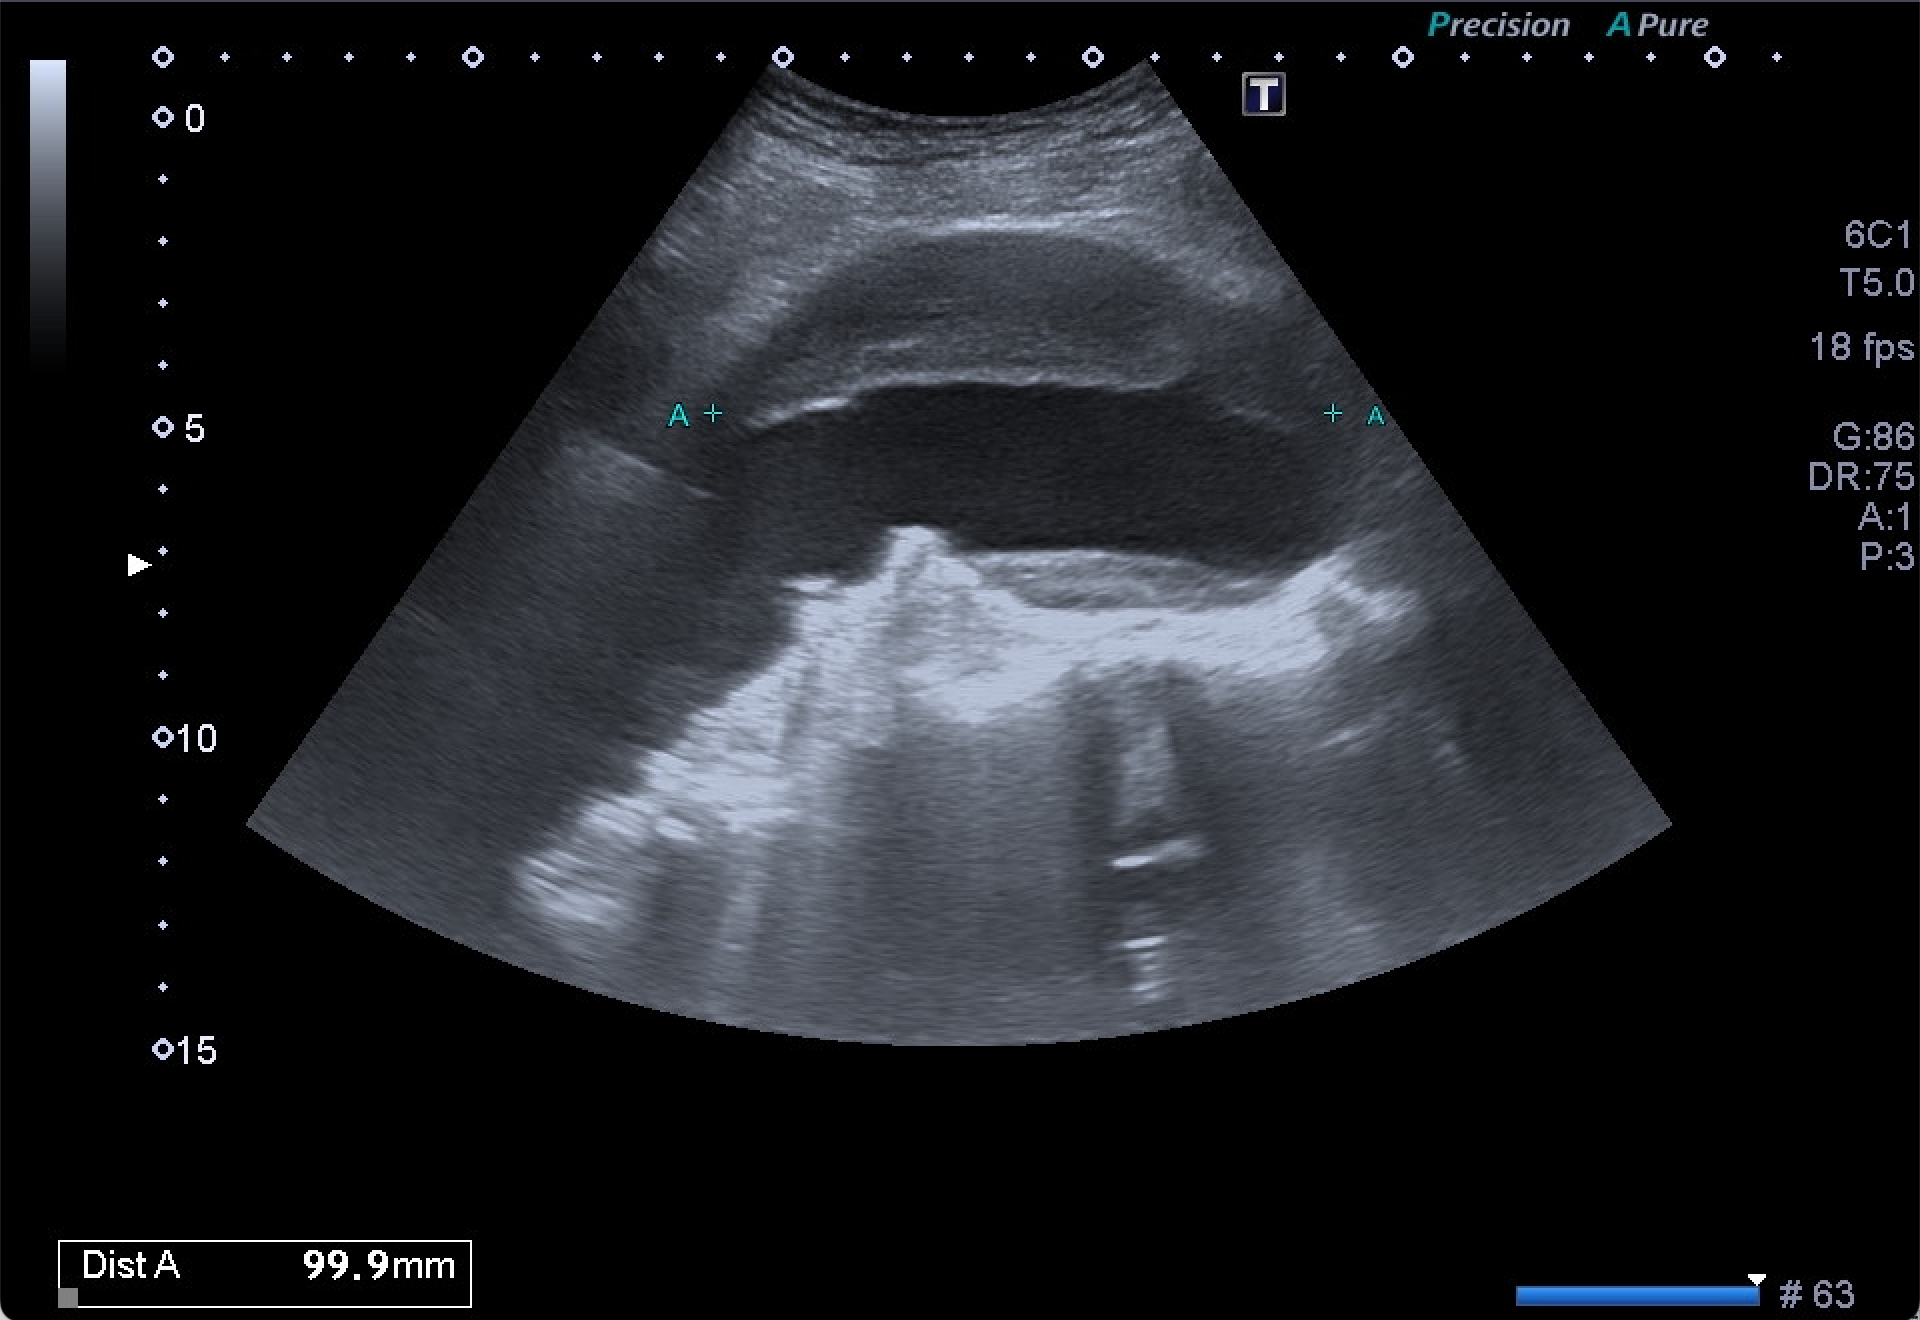

Dados los hallazgos, se completa estudio con AngioTC, confirmando la existencia de aneurisma infrarrenal de 6 mm de diámetro mayor, junto con litiasis renal derecha de 5,5 mm y dilatación de la pelvis renal.